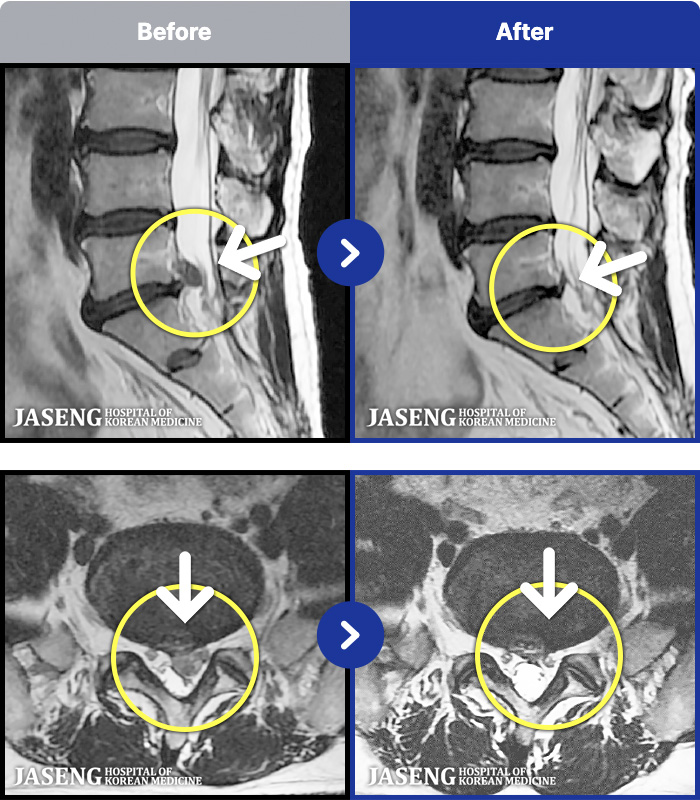

MRI ġ

63 MRI ũ ʸ Ȯϼ.

Ƹ ϰ ־.

õ

ȯ

㸮ũ

[õ] 25.03.18~25.07.22

ȯںп Ǹ ǿ ԿǾ, ο ġ ۿ Ƿ ġḦ Ͻñ ٶϴ.